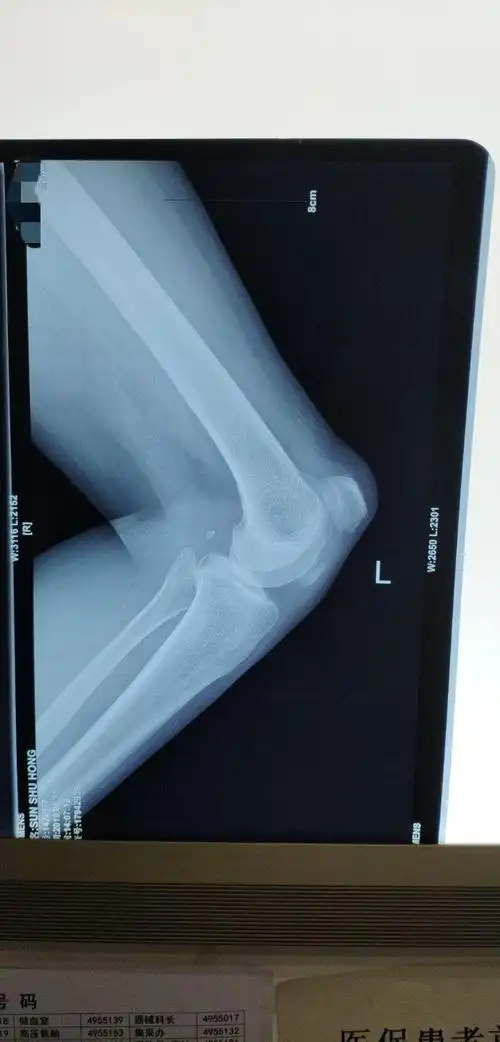

分享一例髌骨骨折

髌骨骨折